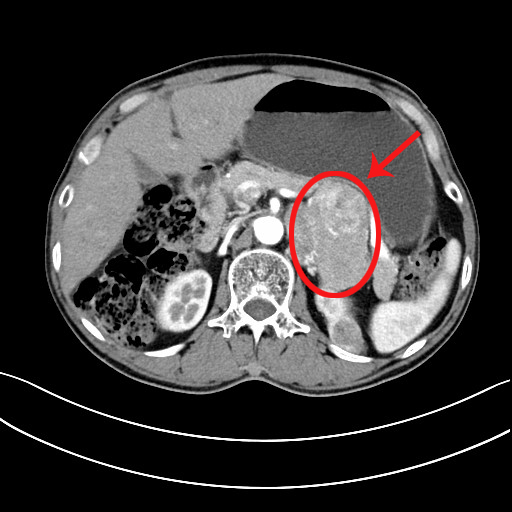

近期,家住内蒙古锡林郭勒的刘先生时感胸口憋闷,伴有头晕症状,在当地医院就诊怀疑是心脏病,经介绍来到首都医科大学附属北京潞河医院泌尿外科就医。刘先生住院后进行了必要检查,经心脏彩超检查并未发现有严重的问题,反而是腹部CT检查发现其左侧肾上腺有肿瘤,最大径12cm。泌尿外科副主任贤少忠随后为刘先生做了血液相关化验检查,发现刘先生的血儿茶酚胺较正常值升高了40倍,贤少忠确定这是一个少见的巨大嗜铬细胞瘤,肿瘤与肾脏、脾脏的血管以及腹腔干紧密粘连,并且病人的嗜铬细胞瘤分泌功能旺盛,会导致血压过山车式的剧烈波动,因此手术风险极大。细心的贤少忠发现,病人的左肾还有一个不起眼的小肿瘤,并且病人的前列腺特异抗原(PSA)是正常值的3倍,这意味着病人可能同时存在肾上腺嗜铬细胞瘤、肾肿瘤、前列腺癌三种肿瘤,这使本来棘手的问题变得更加复杂。

在进行了充分的扩血管、扩容及肠道清洁等准备后,第一阶段进行了腹腔镜下左肾上腺肿瘤切除+左肾肿瘤剜除+经会阴前列腺穿刺活检手术。手术由贤少忠主刀完成,为避免挤压肾上腺瘤体造成血压剧烈波动,他采用了对瘤体扰动最小的经腹入路,迅速暴露肾上腺中央静脉并结扎,切断了激素的入血之路,使后面的手术过程更加平稳。然后他小心翼翼地围绕肿瘤抽丝剥茧,成功地将这枚巨型炸弹完整拆除。由于肾肿瘤位于肾上极的背侧,贤少忠在患者腋后线增加1枚辅助Trocar改行经腰入路,仅用时8分钟便完成了左肾肿瘤剜除手术,将热缺血时间压缩到远低于国际安全阈值(25分钟)。最后,采取超声引导下经会阴前列腺穿刺活检手术。幸运的是术后病理证实左刘先生的肾肿瘤为良性的血管平滑肌脂肪瘤,不幸的是前列腺靶向穿刺1针为恶性。